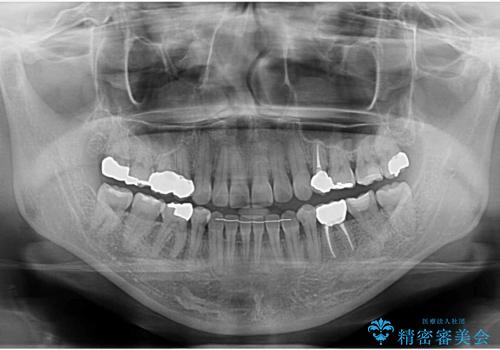

全体的な虫歯治療

- 他院で矯正治療終了後、健診をご希望されました。

神経の治療や詰め物のやり直しなど、全体的な治療を行っています。

左下6番、左上4番は失活していたため、根管治療を行っています。

右上7・左上6:PGAインレー

右上8:PGAクラウン

左上4・左下6・右上56:ジルコニアクラウン

左上7・左下7:emaxインレー

での治療を行っています。

根管治療はDr.大元が行っています。